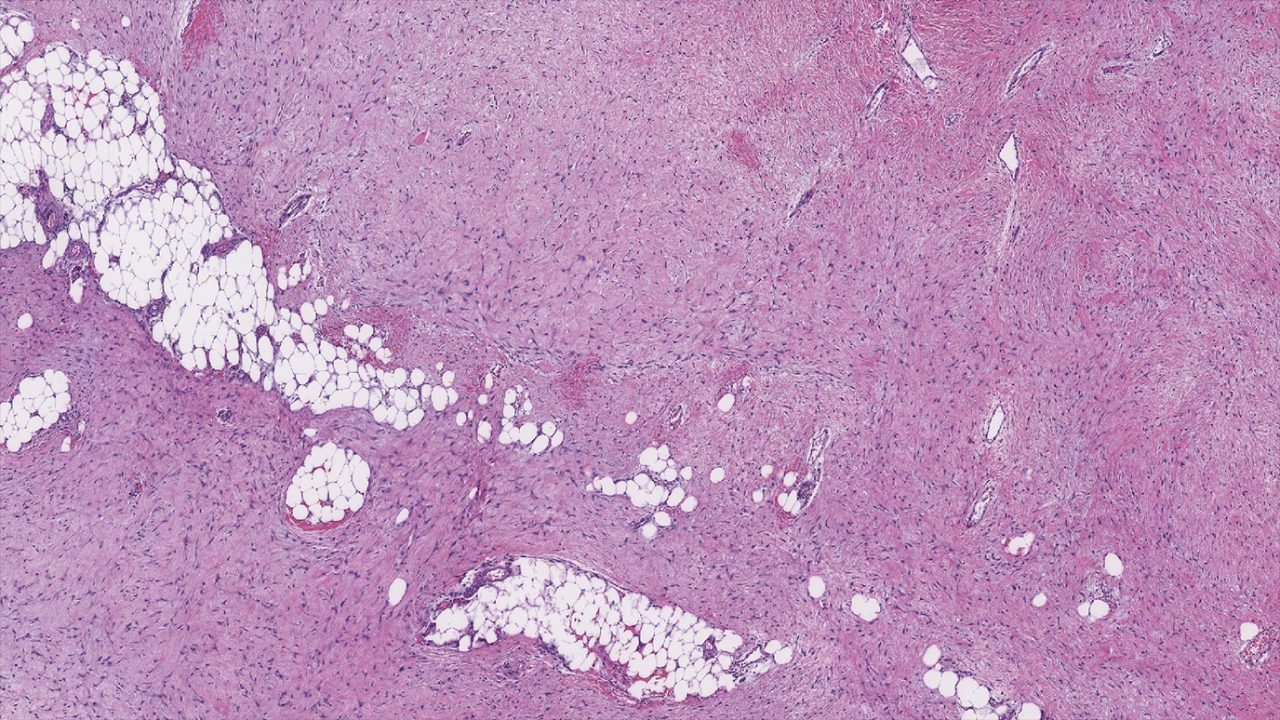

Desmoid tumors are slow-growing, locally invasive tumors that develop in the body’s connective tissues. Also known as aggressive fibromatosis, they’re treated with many of the same therapies that are used on soft tissue cancers like sarcoma, including surgery and chemotherapy.

Not everyone considers desmoid tumors to be cancerous. So, are desmoid tumors benign or malignant? And, how are they usually diagnosed? We asked sarcoma...